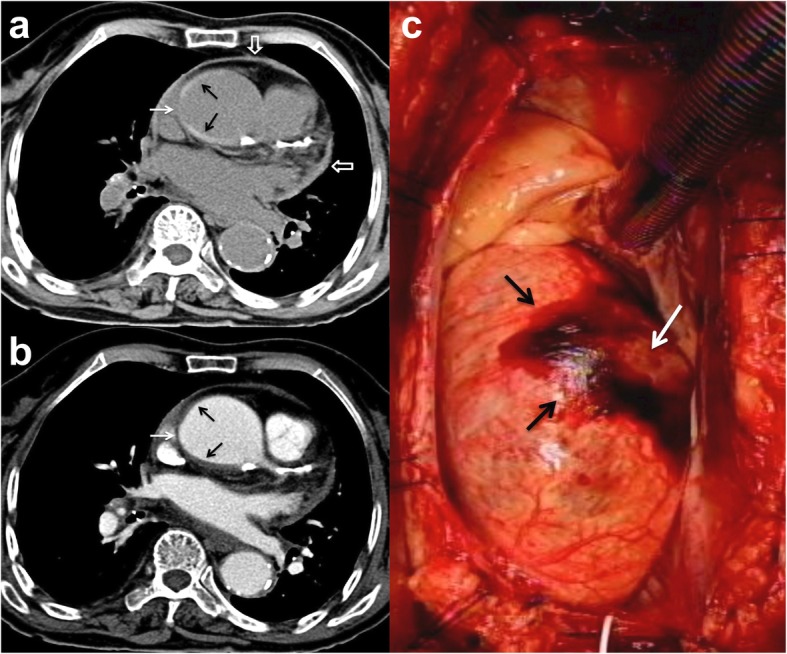

Fig. 4.

a Unenhanced axial CT shows a smooth central defect (white arrow) in the hyper-attenuating crescentic hematoma (black arrows) along the ascending thoracic aorta and minimal hemopericardium. b Enhanced CT shows a smooth focal out-bulging (white arrow) of the aortic lumen corresponding to the defect on unenhanced study and non-enhancing crescentic hematoma (black arrows). Note the absence of intimal flap or contrast medium extravasation. c Surgical findings confirmed ecchymosis at the ascending aorta caused by IMH and focal aortic adventitial defect